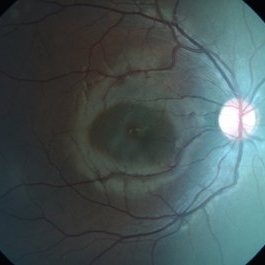

Myopic Degeneration

Sep 10 2014 by Mehul A Shah

Chorio retinal atrophy.

Photographer: Drashti Netralaya

Imaging device: Zeiss FF450

Condition/keywords: myopia